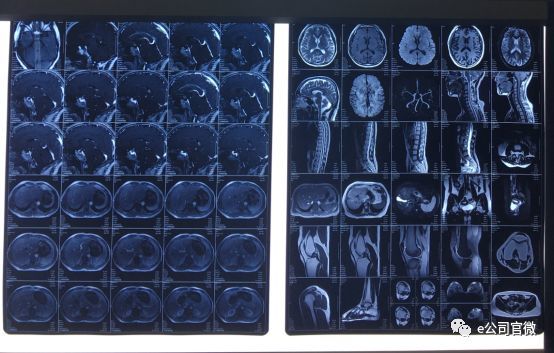

医学中,核磁共振成像是一项常见影像检测手段,与X光、CT相比,核磁共振具有成像参数多、扫描速度快、分辨率高、图像更清晰等优点,而且对人体没有游离辐射损伤,对脑、肝、脾、肾、子宫、卵巢、前列腺等器官以及心脏和大血管都有绝佳的诊断功能,可以帮助医生“看见”不易察觉的早期病变。

展厅中陈列着包括“0.7T”、“1.5T”、“3.0T”等一系列超导磁共振成像产品,工作人员介绍,“0.7T”、“1.5T”、“3.0T”代表磁感应强度的不同,参数越大,成像就越清晰,成像的效率也越高,所对应的产品也越高端。

其中,3.0T超导型磁共振是目前已普及的最高场强磁共振设备,这是公司历时五年、攻克多项关键技术难题取得的成果。2018年1月,公司成为国内第二家取得3.0T超导型磁共振成像系统CFDA注册证的企业,标志着在高端产品中占据一席之地。